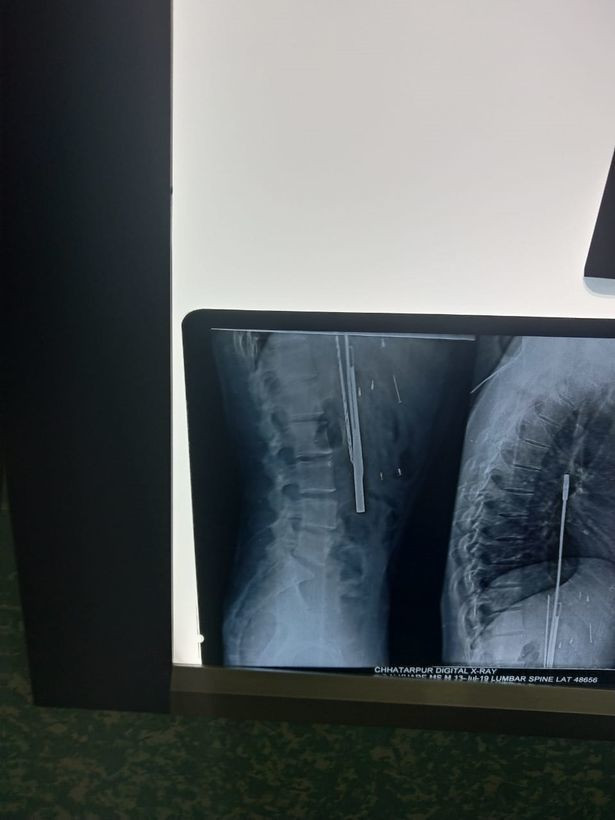

![]() |

| Một phim chụp X-quang cho thấy các vật thể găm trong bụng anh Thakur. |